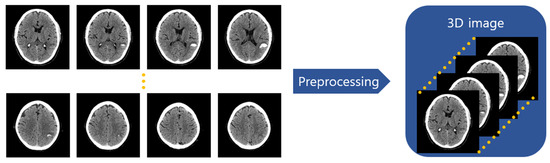

Preprocessing methods such as image normalization and size adjustments, used in existing image captioning studies, were used and supplemented by adding a step to compose the entire sequence of images into a single 3D image, as shown in Figure 3. In this case, the sequences of CT images were unique for each patient, and the number of images in each patient’s sequence varied. According to this, the average number of images per CT scan was checked, and the CT scan’s average image count was approximately 47, with a median value of 49. The maximum number of images in a single 3D image was set to 64. If the number of images was insufficient, post-padding with a black image was carried out, and if exceeded, images from the 65th onwards were excluded.

Figure 3. Preprocessing of sequential 2D CT scan images into 3D images. In the preprocessing, image normalizations and image resize are applied to the CT scan images and the images are stacked into one 3D image following the original order.